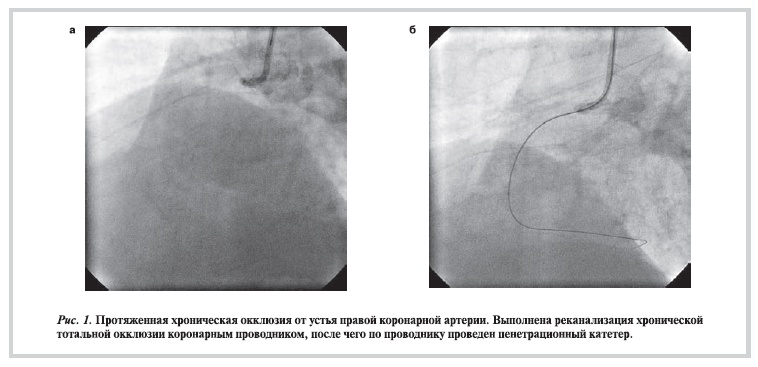

После проведения реканализации ХТО коронарным проводником формировали канал пенетрационным катетером, который вращали вручную. В 81,4% случаев Tornus был успешно проведен в дистальное русло коронарной артерии. Еще у 8 (18,6%) пациентов с выраженным кальцинозом ХТО не удалось провести пенетрационный катетер дистальнее окклюзии, но частично сформированный канал

в ХТО позволил в 2 случаях завести в поражение коронарный баллон и выполнить последующую успешную баллонную ангиопластику и имплантировать коронарный стент. Пример успешной реканализации ХТО правой коронарной артерии представлен ниже (рис. 1—3).

Рисунок 1. Протяженная хроническая окклюзия от устья правой коронарной артерии. Выполнена реканализация хронической тотальной окклюзии коронарным проводником, после чего по проводнику проведен пенетрационный катетер.